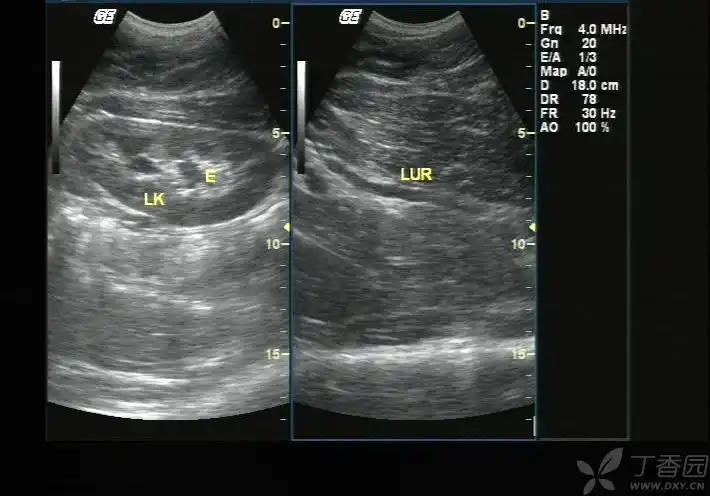

和图 声像图示胆总管(cbd)轻度扩张

门静脉轻度扩张.